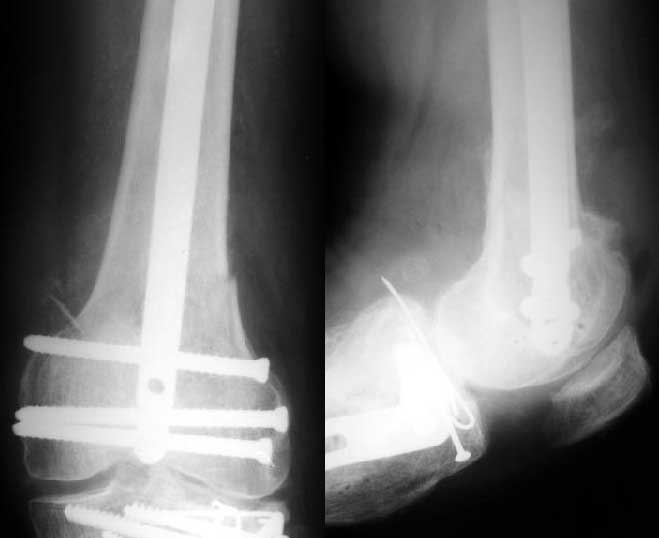

Отправитель: Alexander Chelnokov 28 Декабрь 2003, 21:01

1

2

de> you think you are using antigrade nails for some very low

de> fractures including some intercondylar fractures.

Exactly. It seems the option looks underestimated.

No, i haven't seen such comparisons. However some advantages of closed antegrade nailing vs conventional plating looks self-evident like no site opeining, no bone skeletization, less blood loss, no need for autografting... If you or other colleagues can help me with the references it would be greatly appreciated. I would be interested also to compare ante- vs retrograde nailing for the localization.

I attached an example of C2 fracture with result of the same technique in 5 months.